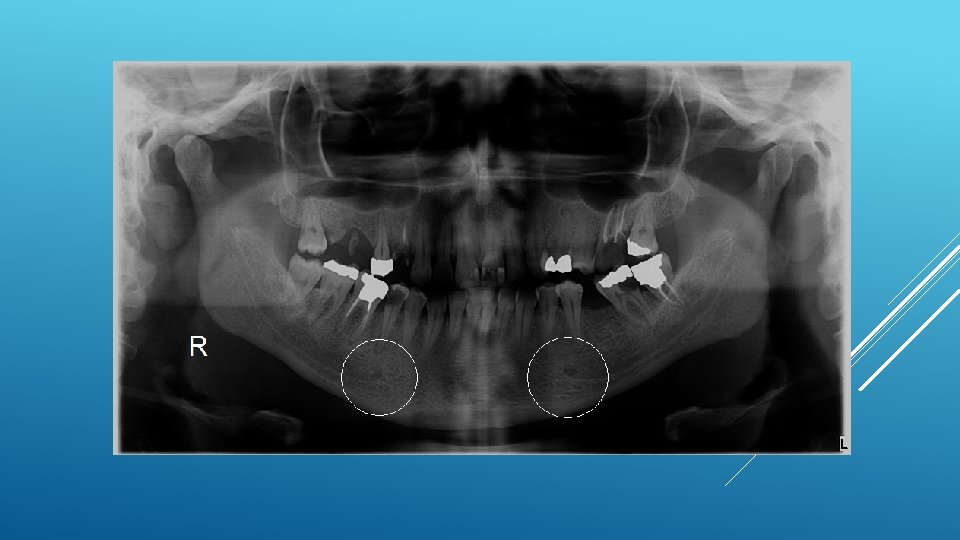

LOCATION AND DIMENSIONS OF THE MENTAL FORAMEN: A RADIOGRAPHIC ANALYSIS BY USING CONE-BEAM COMPUTED TOMOGRAPHY The majority of MF (56%) were located apically between the 2 premolars, and another 35. 7% of MF were positioned below the second premolar. On average, the MF was localized 5. 0 mm from the closest root of the adjacent tooth (range, 0. 3 -9. 8 mm). The mean size of the MF showed a height of 3. 0 mm and a length of 3. 2 mm; however, individual cases showed large differences in height (1. 8 -5. 1 mm) and in length (1. 8 -5. 5 mm). All mental canals exiting the MF demonstrated an upward course in the coronal plane, with 70. 1% of the mental canal presenting an anterior loop (AL) in the axial view. The mean extension of AL in cases with an AL was 2. 3 mm.

RELATIONSHIP BETWEEN THE POSITION OF THE MENTAL FORAMEN AND THE ANTERIOR LOOP OF THE INFERIOR ALVEOLAR NERVE AS DETERMINED BY CONE BEAM COMPUTED TOMOGRAPHY COMBINED WITH MIMICS The parameters were measured, and their values include mean (SD) anterior loop length, 1. 16 (1. 78) mm; anterior loop angle, 19. 13 (26. 89) degrees; inferior alveolar canal diameter, 3. 01 (0. 67) mm; height of the inferior alveolar canal, 10. 32 (1. 56) mm; 2 -dimensional mental foramen diameter, 2. 97 (0. 61) mm; 3 D mental foramen diameter, 2. 95 (0. 59) mm; 2 -dimensional vertical height of the mental foramen, 14. 67 (1. 67) mm; and 3 D vertical height of the mental foramen, 14. 61 (1. 69) mm. The mental foramen was located apically between the first and second premolars in 51. 67% and below the second premolar in 40. 83% of the cases.

THE MENTAL FORAMEN OR "THE CROSSROADS OF THE MANDIBLE. " AN ANATOMIC AND CLINICAL OBSERVATION] [ARTICLE IN FRENCH, GERMAN] THOMAS VON ARX 1 This paper presents a clinical and anatomical review of the mental foramen (MF) based on recent publications (since 1990). Usually, the MF is located below the 2 nd premolar or between the two premolars, but it may also be positioned below the 1 st premolar or below the mesial root of the 1 st molar. At the level of the MF, lingual canals may join the mandibular canal (hence the term "crossroads"). Accessory MF are frequently described in the literature with large ethnic variations in incidence. The emergence pattern of the mental canal usually has an upward and posterior direction. The presence and extent of an "anterior loop" of the mental canal may be overestimated with panoramic radiography. Limited cone-beam computed tomography currently appears to be the most precise radiographic technique for assessment of the "anterior loop". The mental nerve exiting the MF usually has three to four branches for innervation of the soft tissues of the chin, lower lip, facial gingiva and mucosa in the anterior mandible. The clinician is advised to observe a safety distance when performing incisions and osteotomies in the vicinity of the MF.

ANATOMICAL RELATIONSHIP BETWEEN MENTAL FORAMEN, MANDIBULAR TEETH AND RISK OF NERVE INJURY WITH ENDODONTIC TREATMENT he root apex of the mandibular second premolar (70 %), followed by the first premolar (18 %) and then the first molar (12 %), was the closest to the MF. Ninetysix percent of root apices evaluated were >3 mm from the MF. An AL was present in 88 % of the cases. Conclusions: With regards to endodontic treatment, the risk of nerve injury in the vicinity of the MF would appear to be low. However, the high incidence of the AL highlights the need for clinicians to be aware and careful of this important anatomical feature.

ASSESSMENT OF MORPHOLOGICAL AND ANATOMICAL CHARACTERISTICS OF MENTAL FORAMEN USING CONE BEAM COMPUTED TOMOGRAPHY All mental foramina were visualized. Regarding location, 49. 2% of the MFs were located between first and second premolars, 7. 7 distal and 39. 7% coincident to the apex of the mandibular second premolar. The mean MF opening angle was 45. 4° on the right side, and 45. 9° on the left. There were no statistically differences between gender groups with regard to the opening angle degree